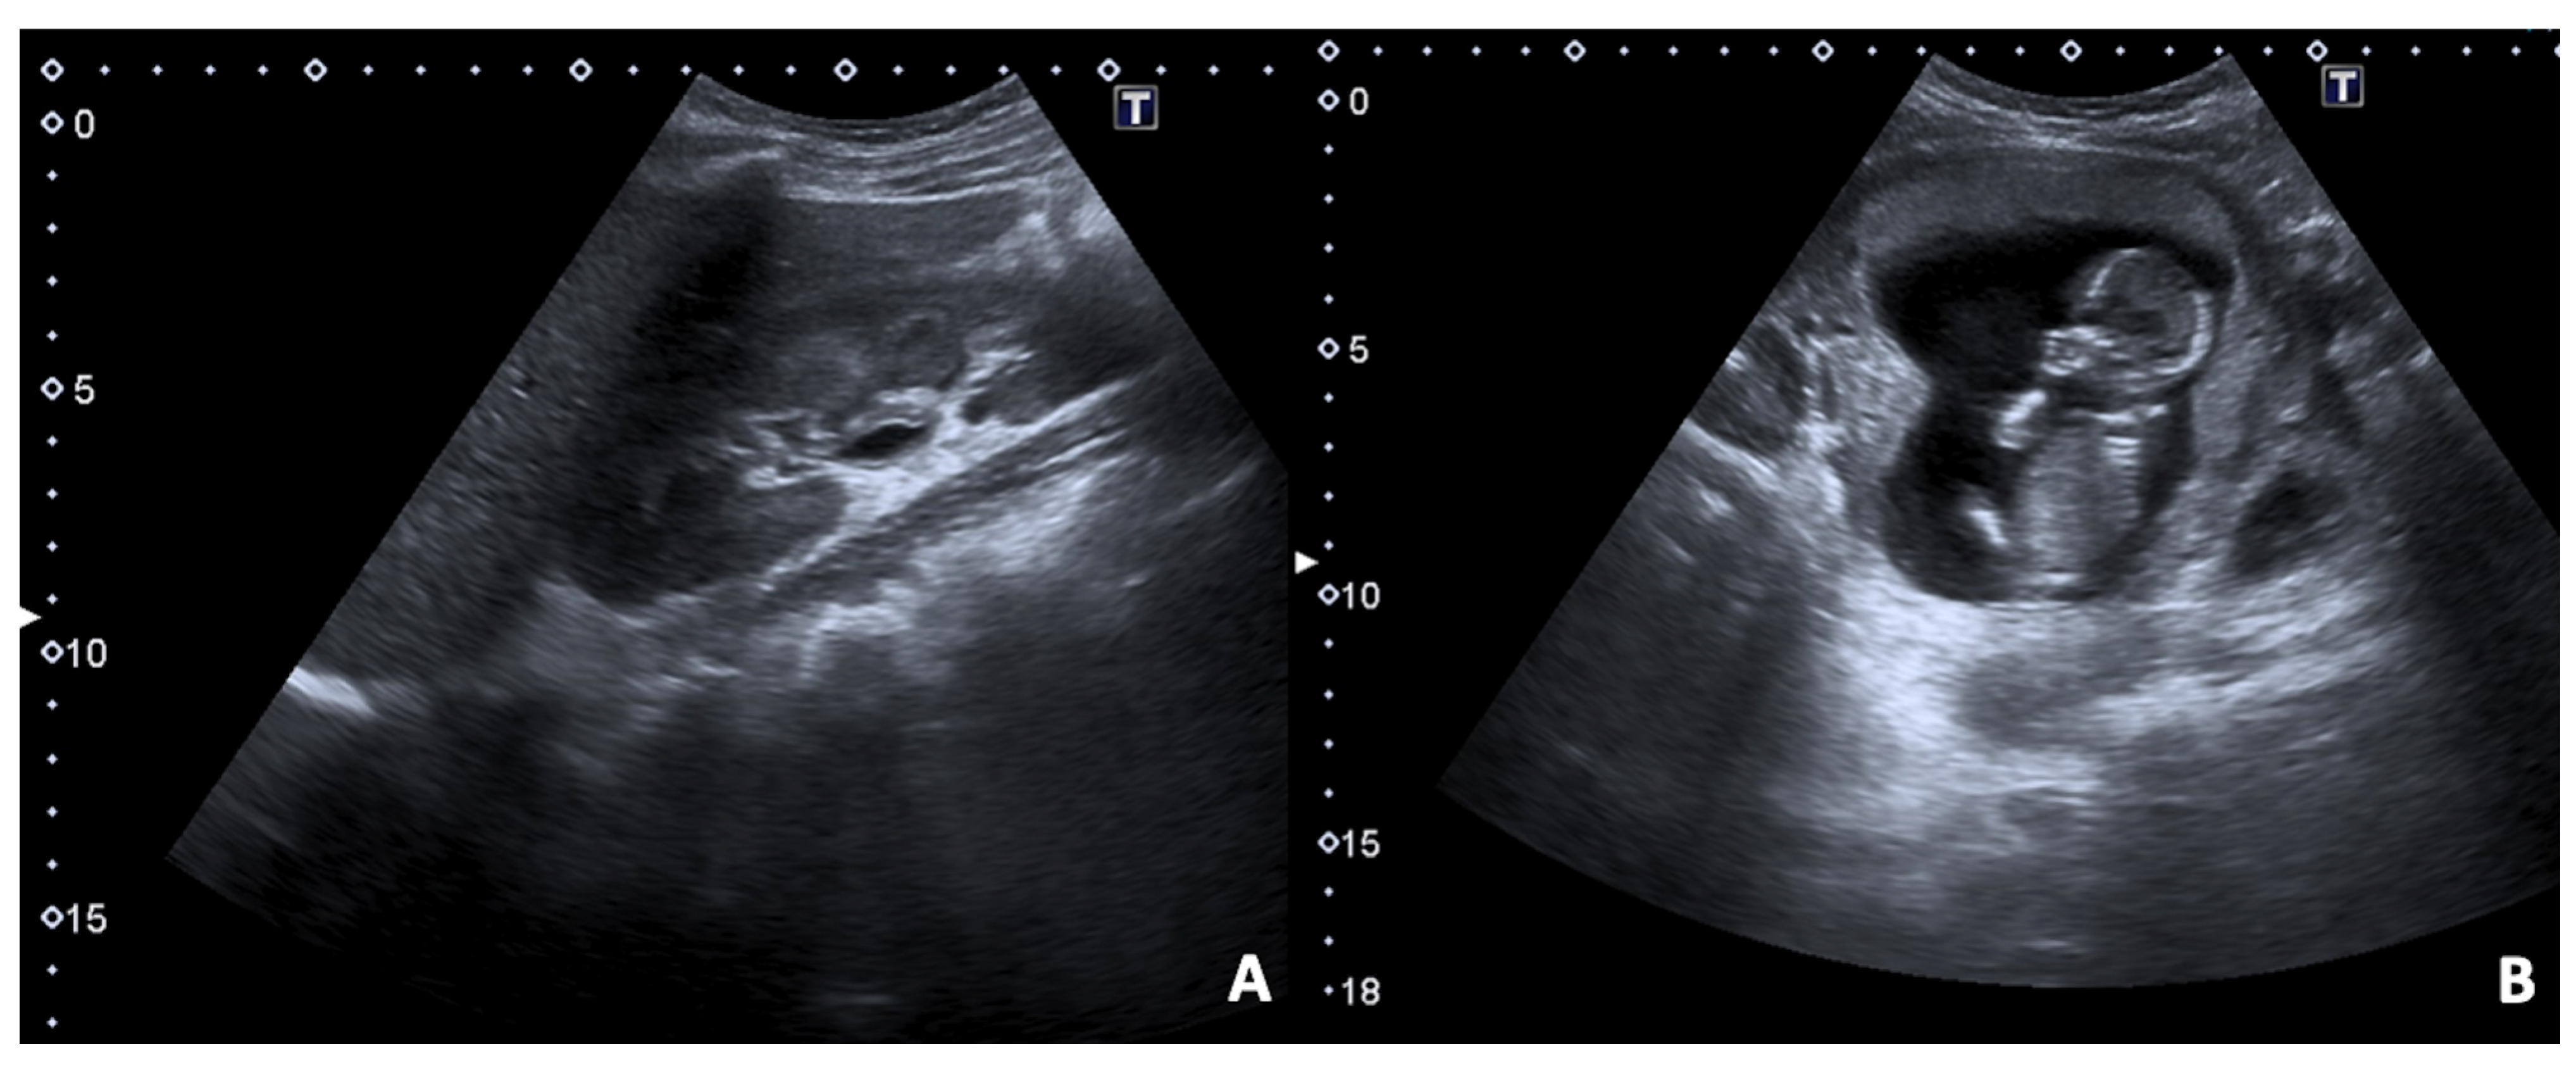

2.1. Spontaneous Abortion

2.2. Ectopic Pregnancy